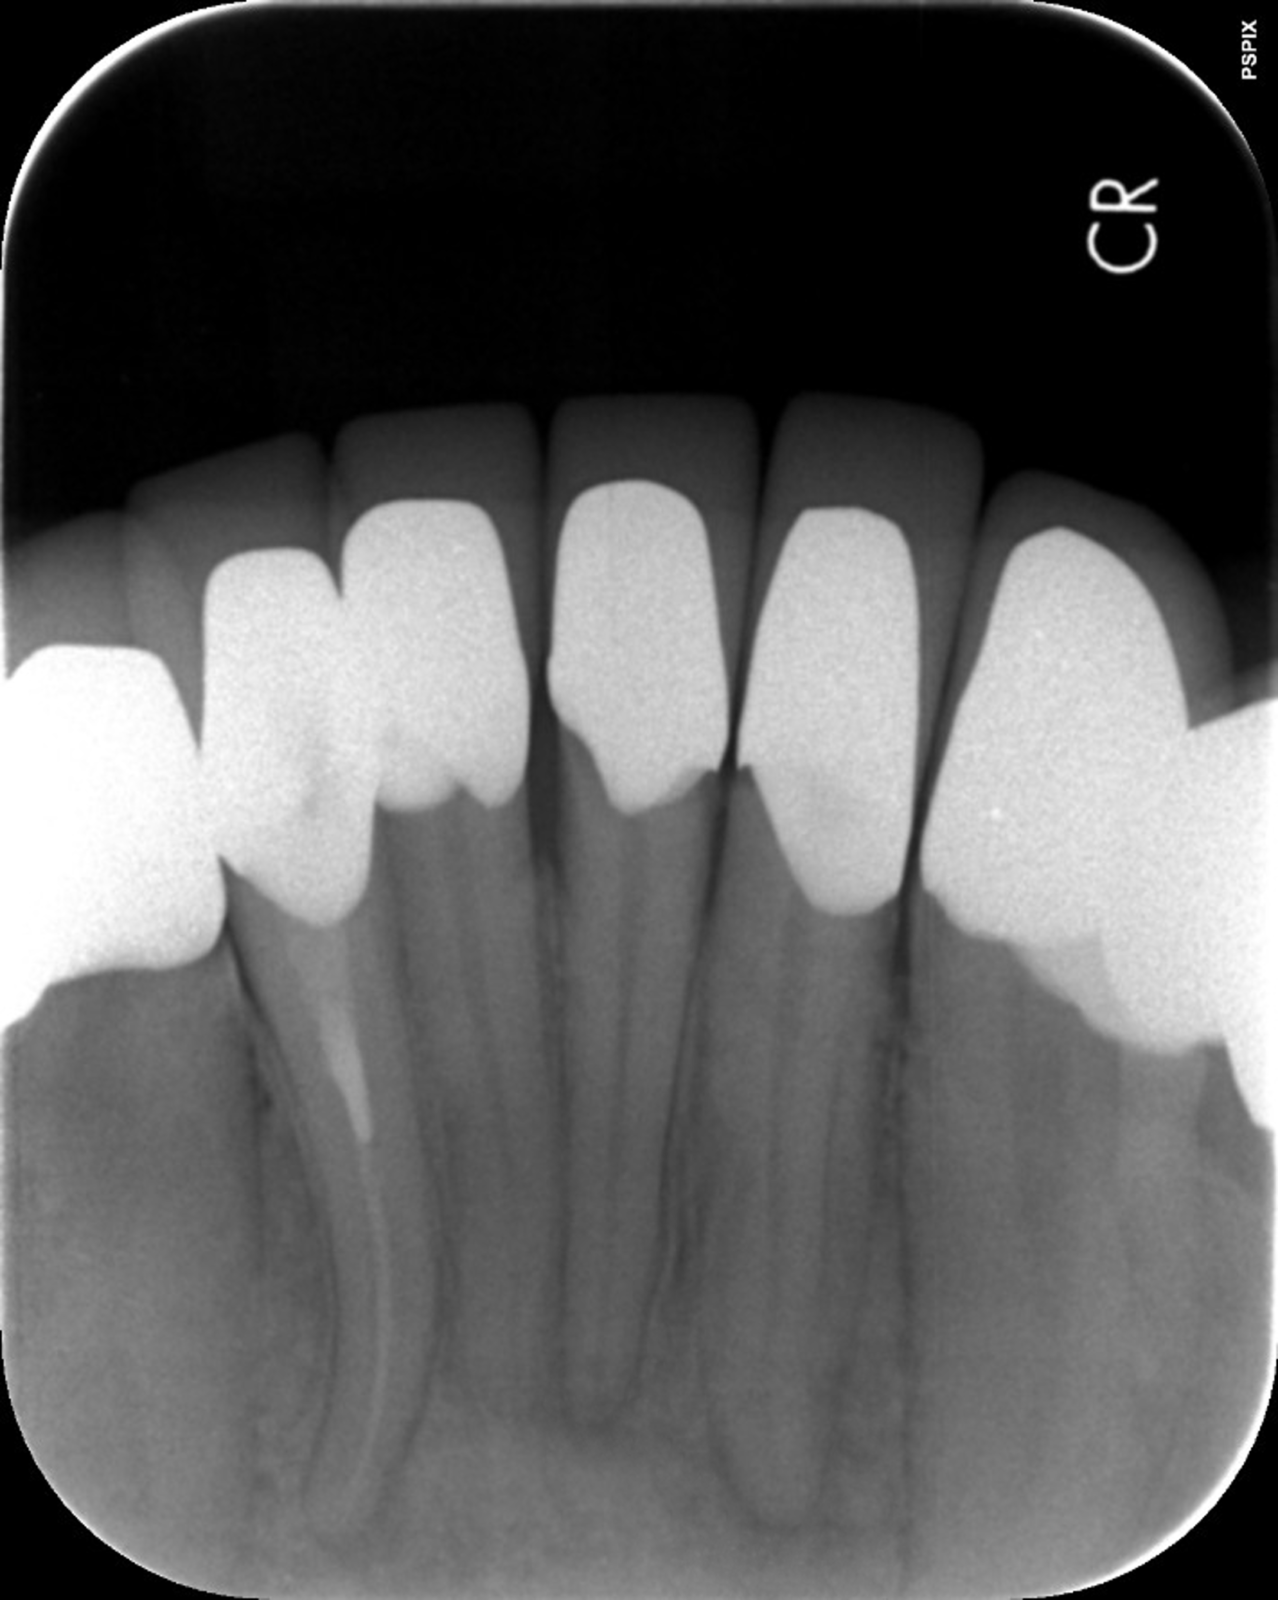

以下の画像は、マイクロスコープで見た患部の様子です。肉眼に比べてどれだけ精度の高い治療ができるか、お分かりいただけると思います。